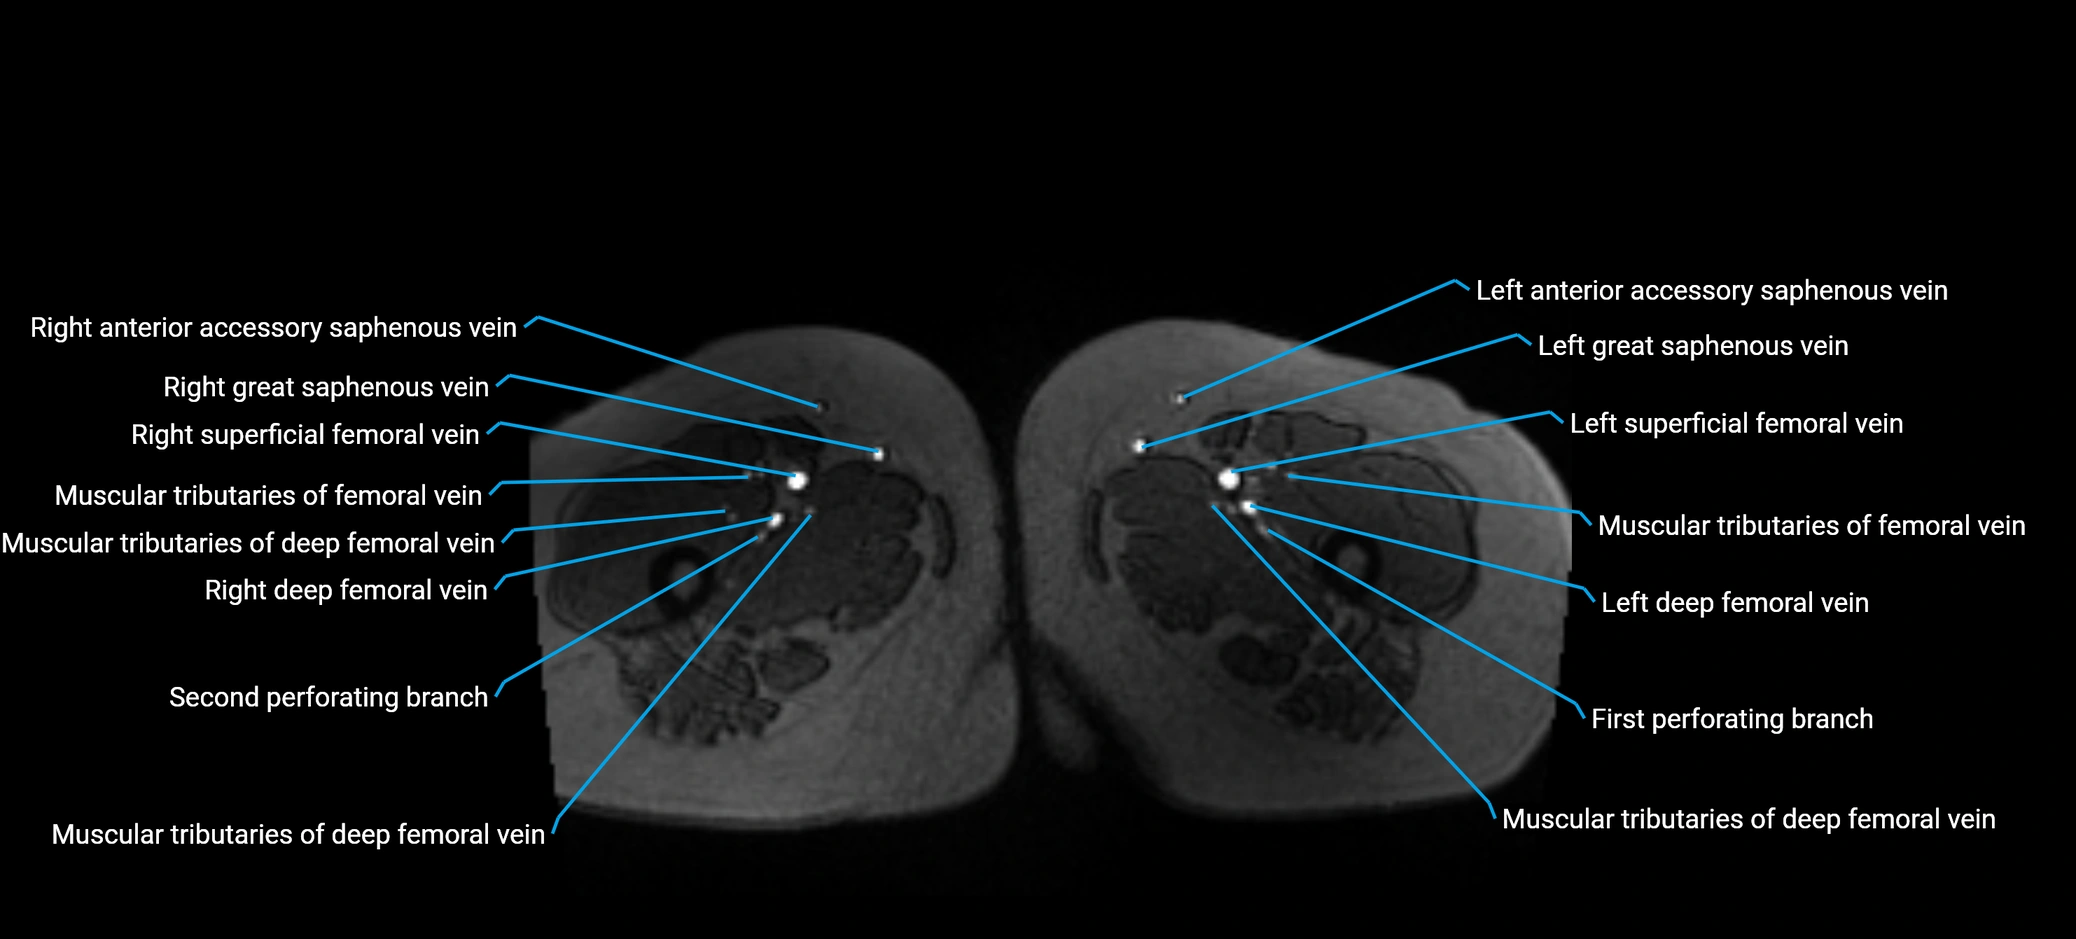

MRI image

image